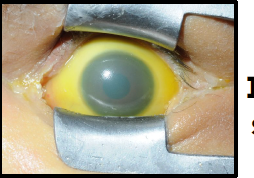

icteric sclera

iris coloboma

blue sclera